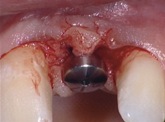

1. 16 h 04 : Incision des minilames pour le décollement.

2. 16 h 09 : Mise en place des vis de cicatrisation.